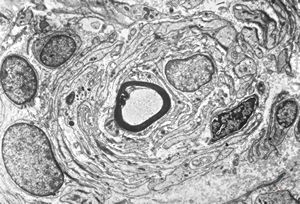

M,13y. | - n.suralis - hypertrophic demyelinizing neuropathy

n.suralis - hypertrophic demyelinizing neuropathy

n.suralis - hypertrophic demyelinizing neuropathy